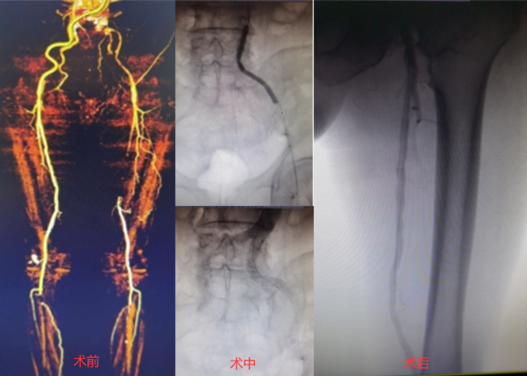

Command 18+Connect flex的导丝组合,融合了这两款导丝的特性,包括强支撑力、耐久性、高穿刺能力、优秀的可控性等特点,能处理临床上的大部分CTO病变。另外,对于部分正向开通困难,如严重钙化,或病变位置不利于正向开通,如髂总开口病变,合理使用逆向导丝技术非常重要。病例3为Command 18联合Connect flex导丝顺利治疗的髂开口闭塞合并股浅长段CTO病变;术中首先采用逆向技术,穿刺股总动脉,开通髂动脉;随后使用Connect flex导丝顺利开通股浅远端长段CTO病变。